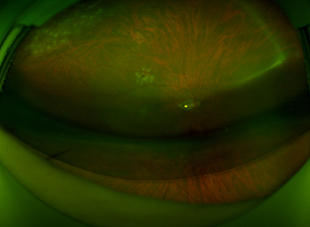

정상망막

정상망막 사진